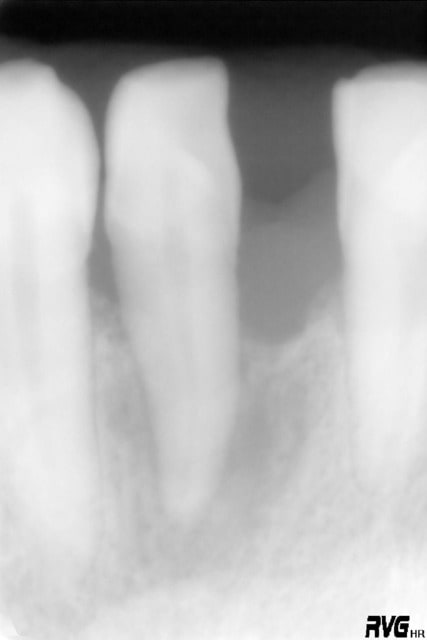

voici donc ce second cas ....

Oui ça ressemble à un canal latéral non obturé, d'autant que le TR parait étrangement rectiligne, même pour une incisive inf.

La cavité d'accès montre qu'une minéralisation rendait le traitement difficile.

Donc oui, un canal oublié.

c'est pas moi qui est fait l'endo ......d'ac avec toi steph ou ....une petite partie de la table vest a disparu ....par contre le parodonte s'est reformé au dessus

le premier cas que j'ai montré à mon avis tiendra sans souci des années et sans contention car la restauration du parodonte sera très importante ....une contention provisoire est suffisante

le second cas est mon premier cas traité ainsi en 1991 ......la dent a parfaitement tenue sa fonction et il y avait une contention par fil continu qui tenait sans problème .....j'ai du extraire la dent en 2004 le patient ayant reçu un choc fatal cette fois !

il n'y a pas eu de prothèses et la dent a tenu 13 ans .....

si je n'avais pas eu cette approche une approche conventionnelle n'aurait rien apporté je pense ....13 ans est-ce trop court ....je ne sais pas.....